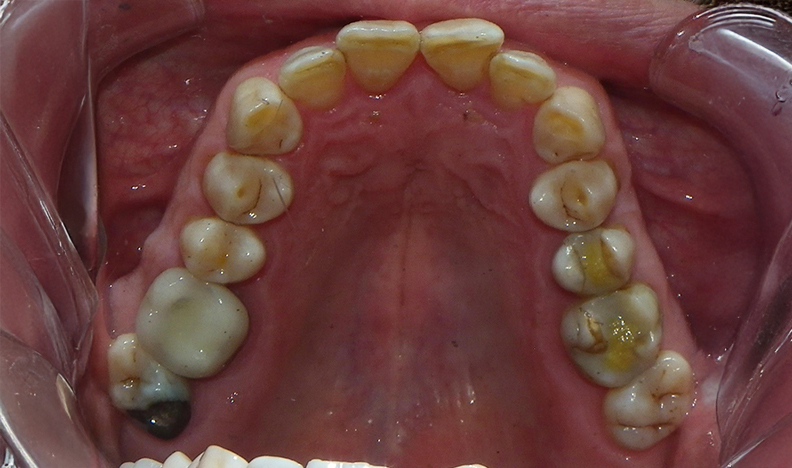

The good airway photo is the mouth of someone who has sleep apnea, breathes through his mouth, and (not seen here) has tongue tension that prevents the tongue from easily resting against the roof of the mouth. You can see that the arch is Omega-shaped with crowding of teeth. Even with orthodontic treatment to straighten the teeth, a cheek/tongue/lip environment like this would likely lead to rapid relapse and a return to pre-orthodontic crookedness.